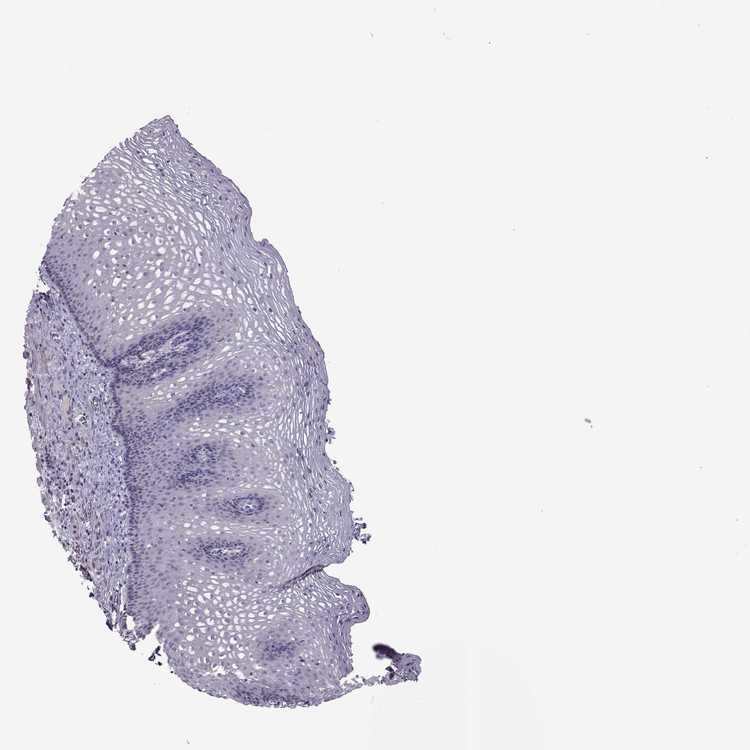

ESOPHAGUS - Antibody stainingi

Antibody staining in the annotated cell types in the current human tissue is reported as not detected, low, medium, or high, based on conventional immunohistochemistry profiling in selected tissues. This score is based on the combination of the staining intensity and fraction of stained cells.

Each image is clickable and will lead to virtual microscopy that enables deeper exploration of all samples and also displays staining intensity scores, fraction scores and subcellular localization as well as patient and tissue information for each sample.

Antibody HPA029725Antibody HPA055572Antibody CAB070192

Squamous epithelial cells Not detectedLowNot detected